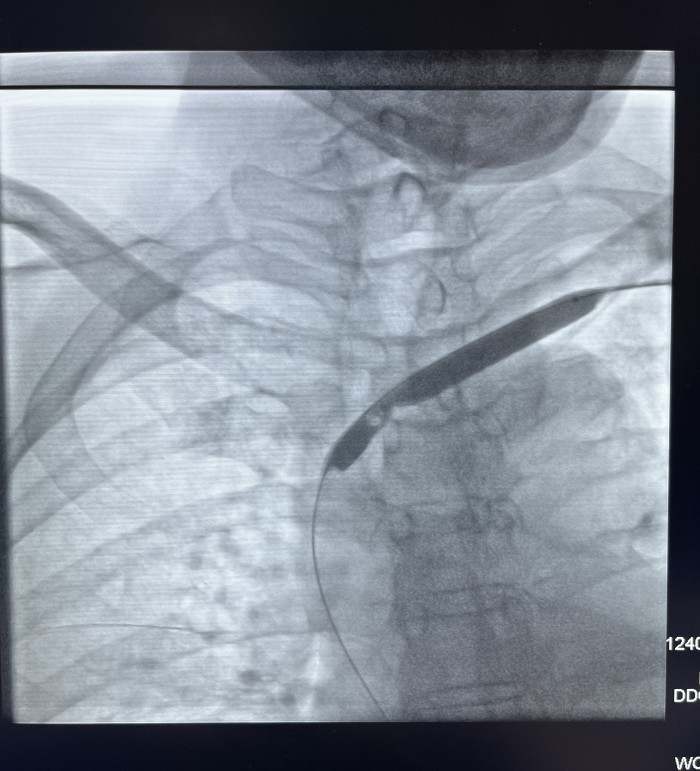

近日,我院介入血管科成功开展一例左头臂静脉重度狭窄球囊成形手术,挽救了患者的左侧桡动脉-头静脉人工

患者赵某,因两侧多囊肾致肾功能衰竭在我院行血液透析三年半。近一年来患者出现血透后左上肢肿胀并伴面颈部表浅静脉怒张,近三月透析时人工内漏内血流量下降。经我院介入血管科副主任芮兵门诊详细询问病史及查体后收治该患者入院,行左上肢CTV及左上肢静脉造影检查显示:左头臂静脉起始部重度狭窄。在芮兵主任医疗团队精心制定手术方案,除手术禁忌后,成功实施了经皮左头臂静脉球囊扩张成形术,术后患者左上肢肿胀明显消退,透析时血流量>200 ml/min,可以完成透析